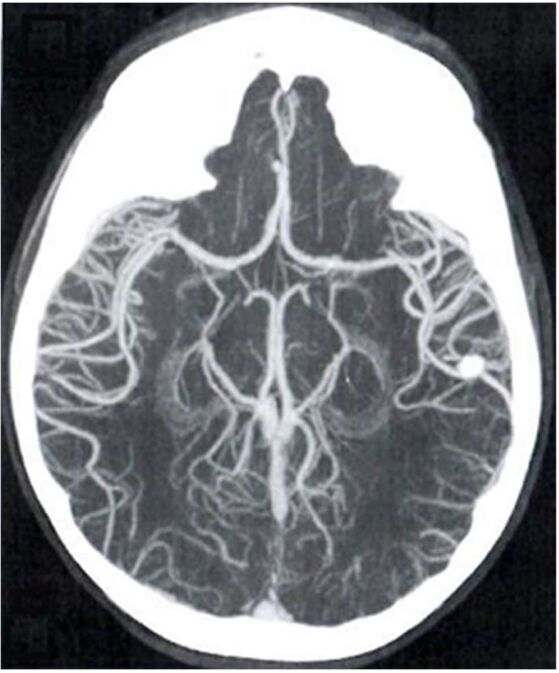

11.如圖是利用下列何者3D影像重建技術?(A)multi-planar reformation(MPR) (B)maximum intensity projection(MIP) (C)shaded surface display(SSD) (D)volume rendering(VR)